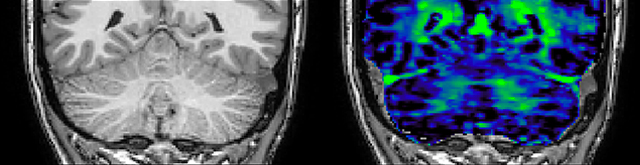

Myelin water imaging (MWI) is a breakthrough technique that was pioneered at UBC for measuring myelin content in the brain, in vivo. “Because the T2 time of water in myelin is much shorter than the T2 of water in the intraand extracellular spaces, we can separate out the myelin water signal.”

The techniques for measuring myelin have changed a lot over the years. “Since we are using the Elition, our myelin water images are much better. We're now acquiring 1 x 2 x 5 mm voxels and displaying at 1 x 1 x 2.5 mm. For a whole brain we can now measure the fraction of water in the myelin component in only about five or six minutes,” Dr. MacKay says.

Dr. Rauscher says, “For MWI we perform 3D T2 with 32 or more echoes. This used to take a long time, but with Compressed SENSE we can decrease this to ten minutes for the whole head. Because of the large field of view (FOV) on the readout direction, we even get information from the brainstem, which we previously missed when we were using the GRASE approach. Having the whole head scan is nice because it has spatial resolution, orientation and FOV that are comparable to the standard 3D clinical MS scans, including the FLAIR and 3D T2, and a 3D T1 for brain volume.”

T1 - weighted

Myelin water imaging - T1 weighted

Myelin water imaging (echo 1)

Myelin water imaging with SENSE

Myelin water imaging with Compressed SENSE

With SENSE

With Compressed SENSE

Acquired resolution:

1 x 2 x 5 mm3

1.5 x 2 x 3 mm3

Number of echoes:

32 or 48

56

Echo spacing:

10 ms or 8 ms

7 ms

T1 - Weighted, Myelin Water Fraction Superimposed

MWI Spinal cord coverage

Spinal cord coverage

MWI Smaller, more isotropic voxels

Smaller, more isotropic voxels

MWI Excellent detail in quantitative maps

Excellent detail in quantitative maps

Images courtesy of Adam Dvorak, Department of Physics and Astronomy, University of British Columbia

20%

Myelin water fraction

0%